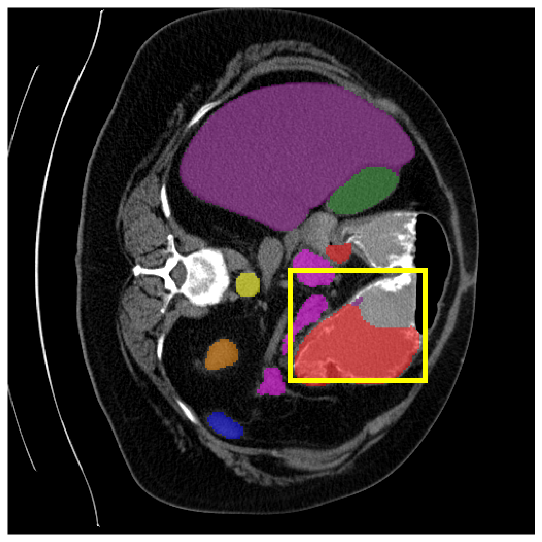

To demonstrate the superiority of our method, additional qualitative comparison results for the ACDC and Synapse datasets are presented in Fig. 6, Fig. 7, respectively. Notably, in the case of GB, the quantitative results in Fig. 7 show relatively lower performance in ‘only ’. However, the visualization results in Fig. 7 reveal instances where the enhanced images identified GB regions that the original images failed to segment, albeit with some boundary over-segmentation. In such scenarios, our proposed method successfully leveraged the information from enhanced images to achieve more accurate GB segmentation. Note that this finding underscores the fact that even when quantitative performance metrics appear lower, the additional information provided by enhanced images can be valuable in the actual segmentation process.

4.3.2 Visual Comparisons

Visualization of our method on the Synapse and ACDC datasets is shown in Fig. 3(a) and Fig. 3(b). For the Synapse dataset illustrated in Fig. 3(a), FCT failed to accurately segment SM and GB, while MERIT achieved precise segmentation of SM but struggled with GB. In contrast, our method achieved accurate segmentation of both SM and GB. Regarding the ACDC dataset shown in Fig. 3(b), while previous methods achieve comparable segmentation of the Myo and LV to the GT, they exhibit noticeable errors on the RV, including invasion into adjacent organs and misrecognition. On the other hand, our method accurately segments across all three structures Myo, LV, and RV, performing as precisely as the GT. We demonstrate the superiority of our method quantitatively and qualitatively.